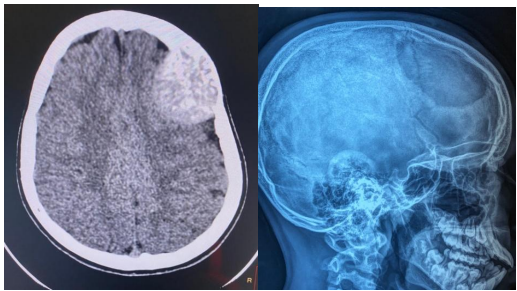

2/Decompressive craniectomy due to stroke (as spontaneous intra cranial haemorrhage or infarction).

Fig 4 and 5 Craniectomy for stroke patients

Fig 6 &7: Free bone flap embedded in the anterior abdominal wall(subcutaneous pocket) .